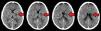

Caso clÃnicoUn paciente masculino de 57años de edad, sin otro factor de riesgo cardiovascular que ex-tabaquismo (22paquetes/año, suspendiendo 14años atrás), ingresa a nuestra institución presentando un cuadro de 45min de evolución consistente en disartria severa, paresia facial derecha severa y paresia braquicrural derecha leve. La primera evaluación médica fue realizada por profesionales de la guardia de emergencias, quienes refirieron que el paciente padecÃa afasia. Veinte minutos tras su ingreso, el puntaje de ictus del NIHSS evaluado por un neurólogo era de 6 (disartria 2 puntos, paresia facial 2, paresia braquial 1, paresia crural 1). La presión arterial (PA) de ingreso fue de 150/90. Con 60min de evolución se realizó una tomografÃa cerebral (TC) con angiotomografÃa (ATC) cerebral (fig. 1) y de vasos de cuello que no demostró sangrado ni lesión isquémica evidente, logrando un puntaje de Alberta Stroke Programe Early CT Score (ASPECTS)1 de 10. En la ATC cerebral no se observó obstrucción, y el puntaje Collateral Score2 fue de 3. En la ATC de vasos de cuello no se observaron estenosis ni lesiones ateroscleróticas. Una reevaluación realizada a las 1:30h de evolución constató una mejorÃa espontánea del cuadro clÃnico, con una reducción de NIHSS a 3 (disartria moderada 1, paresia facial moderada 1, paresia braquial derecha leve 1) en contexto de PA 150/80. Como parte del protocolo de atención, el paciente contaba con dos vÃas periféricas antebraquiales (una en cada brazo) con un goteo lento de solución fisiológica para asegurar su permeabilidad. En ese momento, familiares acompañantes refirieron que minutos antes de la evaluación se hallaba completamente asintomático sin déficit para ellos evidente. Ante tal revelación, llevando 2h de evolución, se realiza maniobra de Trendelenburg y apertura de la infusión de solución fisiológica «a chorro», elevándose la PA a 170/90 y desapareciendo todo déficit neurológico. Media hora después, al agotarse los reservorios de solución fisiológica, y aunque permanecÃa en posición de Trendelenburg, el cuadro deteriora nuevamente volviendo al estado clÃnico inmediatamente anterior con NIHSS de 3, esta vez en contexto de PA 160/80. Se repone infusión de solución fisiológica y el cuadro nuevamente evoluciona favorablemente con NIHSS de 0 y PA de 176/90. El paciente permanece en monitoreo estricto y clÃnicamente estable hasta cumplidas las 3h de evolución, donde a pesar de infusión de solución salina y posición de Trendelenburg la presión arterial desciende a 160/90 y el NIHSS deteriora a 3, presentando siempre el mismo déficit clÃnico (disartria leve-moderada, paresia derecha facial moderada, paresia braquial derecha moderada). Considerando la posibilidad de una trombosis suboclusiva de pequeña arteria con perfusión de miseria (dependiente de PA elevada), se decidió iniciar infusión de Alteplase (dosis plena total 72mg, 10% en bolo endovenoso y el 90% restante en infusión continua a lo largo de una hora). Durante la infusión la PA osciló entre 165 y 158 (sistólica) y 90 a 86 (diastólica). Durante toda la infusión el paciente permaneció en decúbito dorsal a 0 grados respecto al suelo. La evaluación secuencial de NIHSS fue: 3 puntos (basal), 2 puntos (15min de infusión), 0 puntos (30 y 45min de infusión). Al final de la infusión, con PA 160/80, se objetiva nueva fluctuación del cuadro clÃnico, presentando nuevamente NIHSS de 3. A pesar de que el cuadro clÃnico sugerÃa una topografÃa lacunar, dado que al ingreso del paciente el médico que le recibe refirió que el paciente presentaba afasia, ante la posibilidad de estenosis de ramas distales de la arteria cerebral media izquierda se decide realizar angiografÃa digital en busca de estenosis, procedimiento realizado a las 5h 30min, descartando con dicho estudio la presencia de estenosis silviana proximal y distal. Finalizada la angiografÃa digital, se constata que el paciente presentaba un NIHSS de 0 puntos. Por último, desde la sala de hemodinamia fue trasladado para la realización de un protocolo corto de resonancia (secuencias FLAIR, susceptibilidad magnética, difusión y ADC) donde se apreció una lesión isquémica aguda en topografÃa lenticulocapsular izquierda de 26mm de diámetro máximo con restricción de la difusión, ya visible nÃtidamente en secuencia FLAIR, y sin sangrados según susceptibilidad magnética (fig. 2); la RM fue realizada habiendo transcurrido 6h y 40min desde el inicio del cuadro. El paciente ingresó a la unidad de cuidados crÃticos a las 7h de evolución para continuidad de su atención y monitoreo. Se logró estabilizar la presión mediante infusión de solución fisiológica e infusión continua de noradrenalina. A las 24h, sin mediar complicación alguna ni fluctuaciones en presión arterial, el paciente presentaba un NIHSS de 3 (disartria leve, paresia facial central derecha leve, paresia del miembro superior derecho leve). La TC realizada a las 24h post-trombólisis como control rutinario (fig. 3) demostró la presencia de una lesión hipodensa lenticulocapsular izquierda en idéntica topografÃa a la evidenciada en la resonancia magnética, y no se observaron lesiones compatibles con sangrado. Durante la internación se realizó un ecocardiograma transtorácico que informó diámetros, espesores y función del ventrÃculo izquierdo conservado, sin valvulopatÃas ni dilatación auricular izquierda. El alta fue otorgada tras cumplir 6dÃas de internación, y se indicó continuar en forma ambulatoria con ácido acetilsalicÃlico 100mg/dÃa, atorvastatina 20mg/dÃa y enalapril 5mg/dÃa. Su NIHSS al alta fue de 1 (por presentar solo disartria leve). Al mes del evento el paciente ya no presentaba disartria, su NIHSS era de 0 y su puntaje en la escala modificada de Rankin era 0. Se solicitó un monitoreo Holter ambulatorio, pero el paciente no retornó a consulta posteriormente.